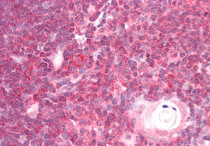

ARG63911 anti-DDX6 antibody IHC-P image

Immunohistochemistry: Paraffin-embedded Human cortex tissue. Antigen Retrieval: Steam tissue section in Citrate buffer (pH 6.0). The tissue section was stained with ARG63911 anti-DDX6 antibody at 5 µg/ml dilution followed by AP-staining.